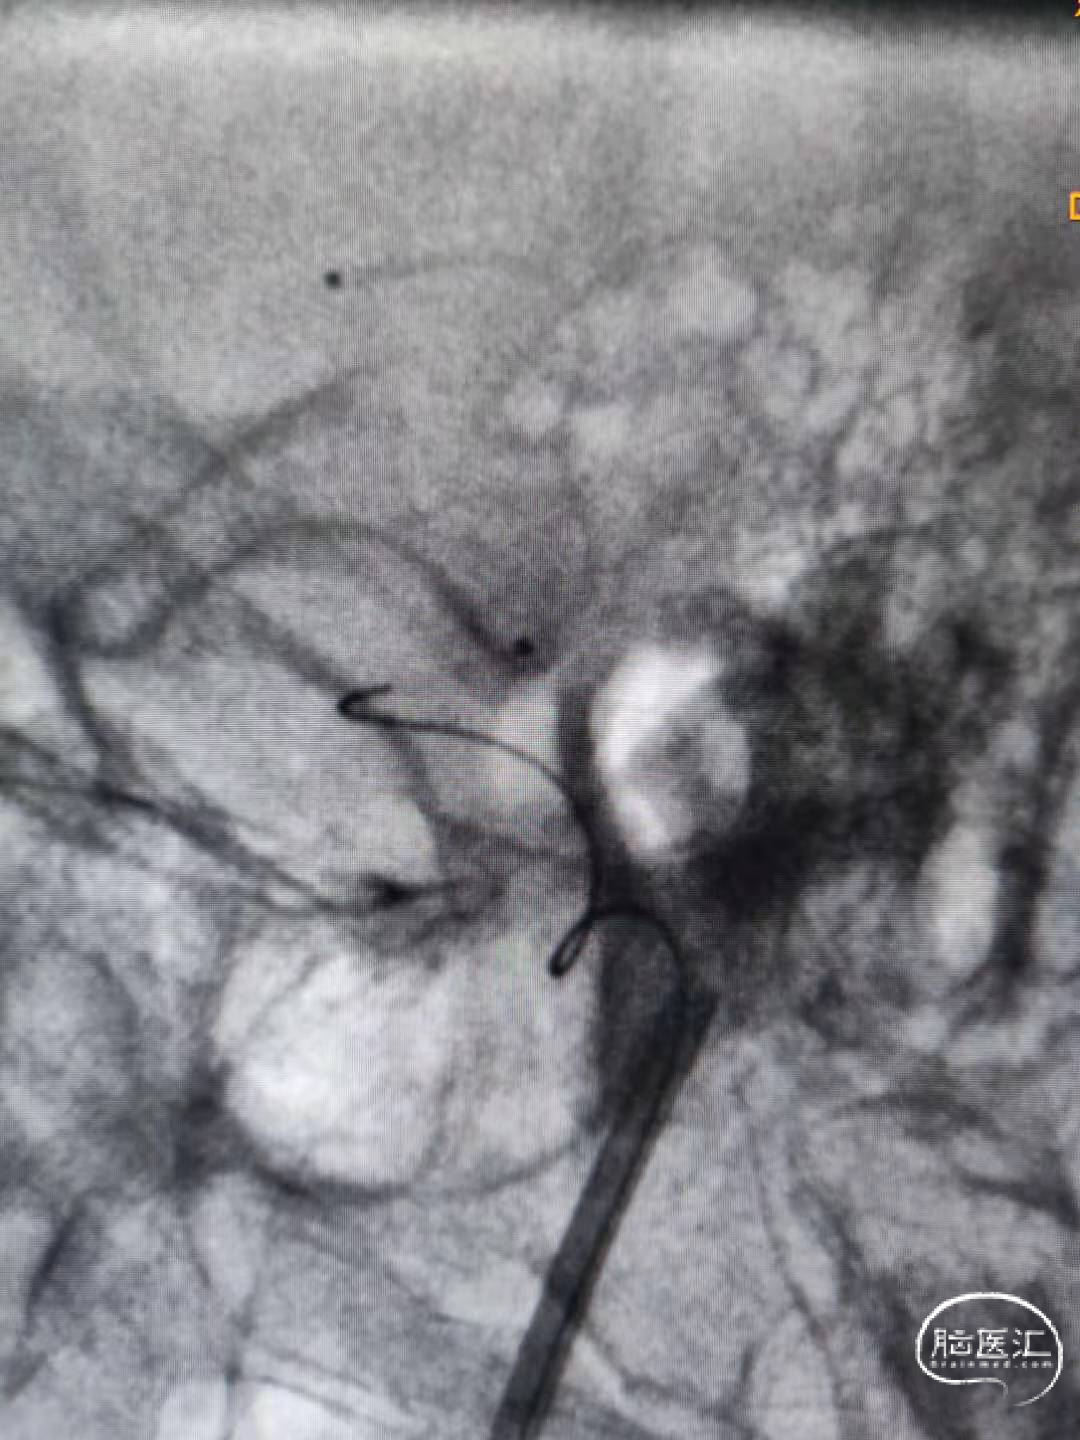

1、与术前分析的一致,由于上支干与M1成角以及瘤颈很宽等因素,微导管超选上支干很困难。最终选择微导丝及微导管瘤体内成袢进入上支干很远后再缓慢逐步回撤微导管解袢。(该步骤风险很大,因为动脉瘤破裂点在瘤顶部,操作时要对微导丝及微导管有精确的掌控能力)。术中使用SL-10微导管及Synchro-14导丝。

2、随后将第二根微导管送至动脉瘤内。使用该导管的目的是要经此微导管推入一枚成篮圈来保护未被支架覆盖的下支干。(因为支架释放后穿网眼的微导管操控性受限,很难形成对下支干良好保护的弹簧圈篮。)

使用SL-10微导管和7*30弹簧圈。成篮满意后释放Atlas 3.0*15支架。支架释放并打开顺利,随后将支架导管穿网眼送入动脉瘤腔内。